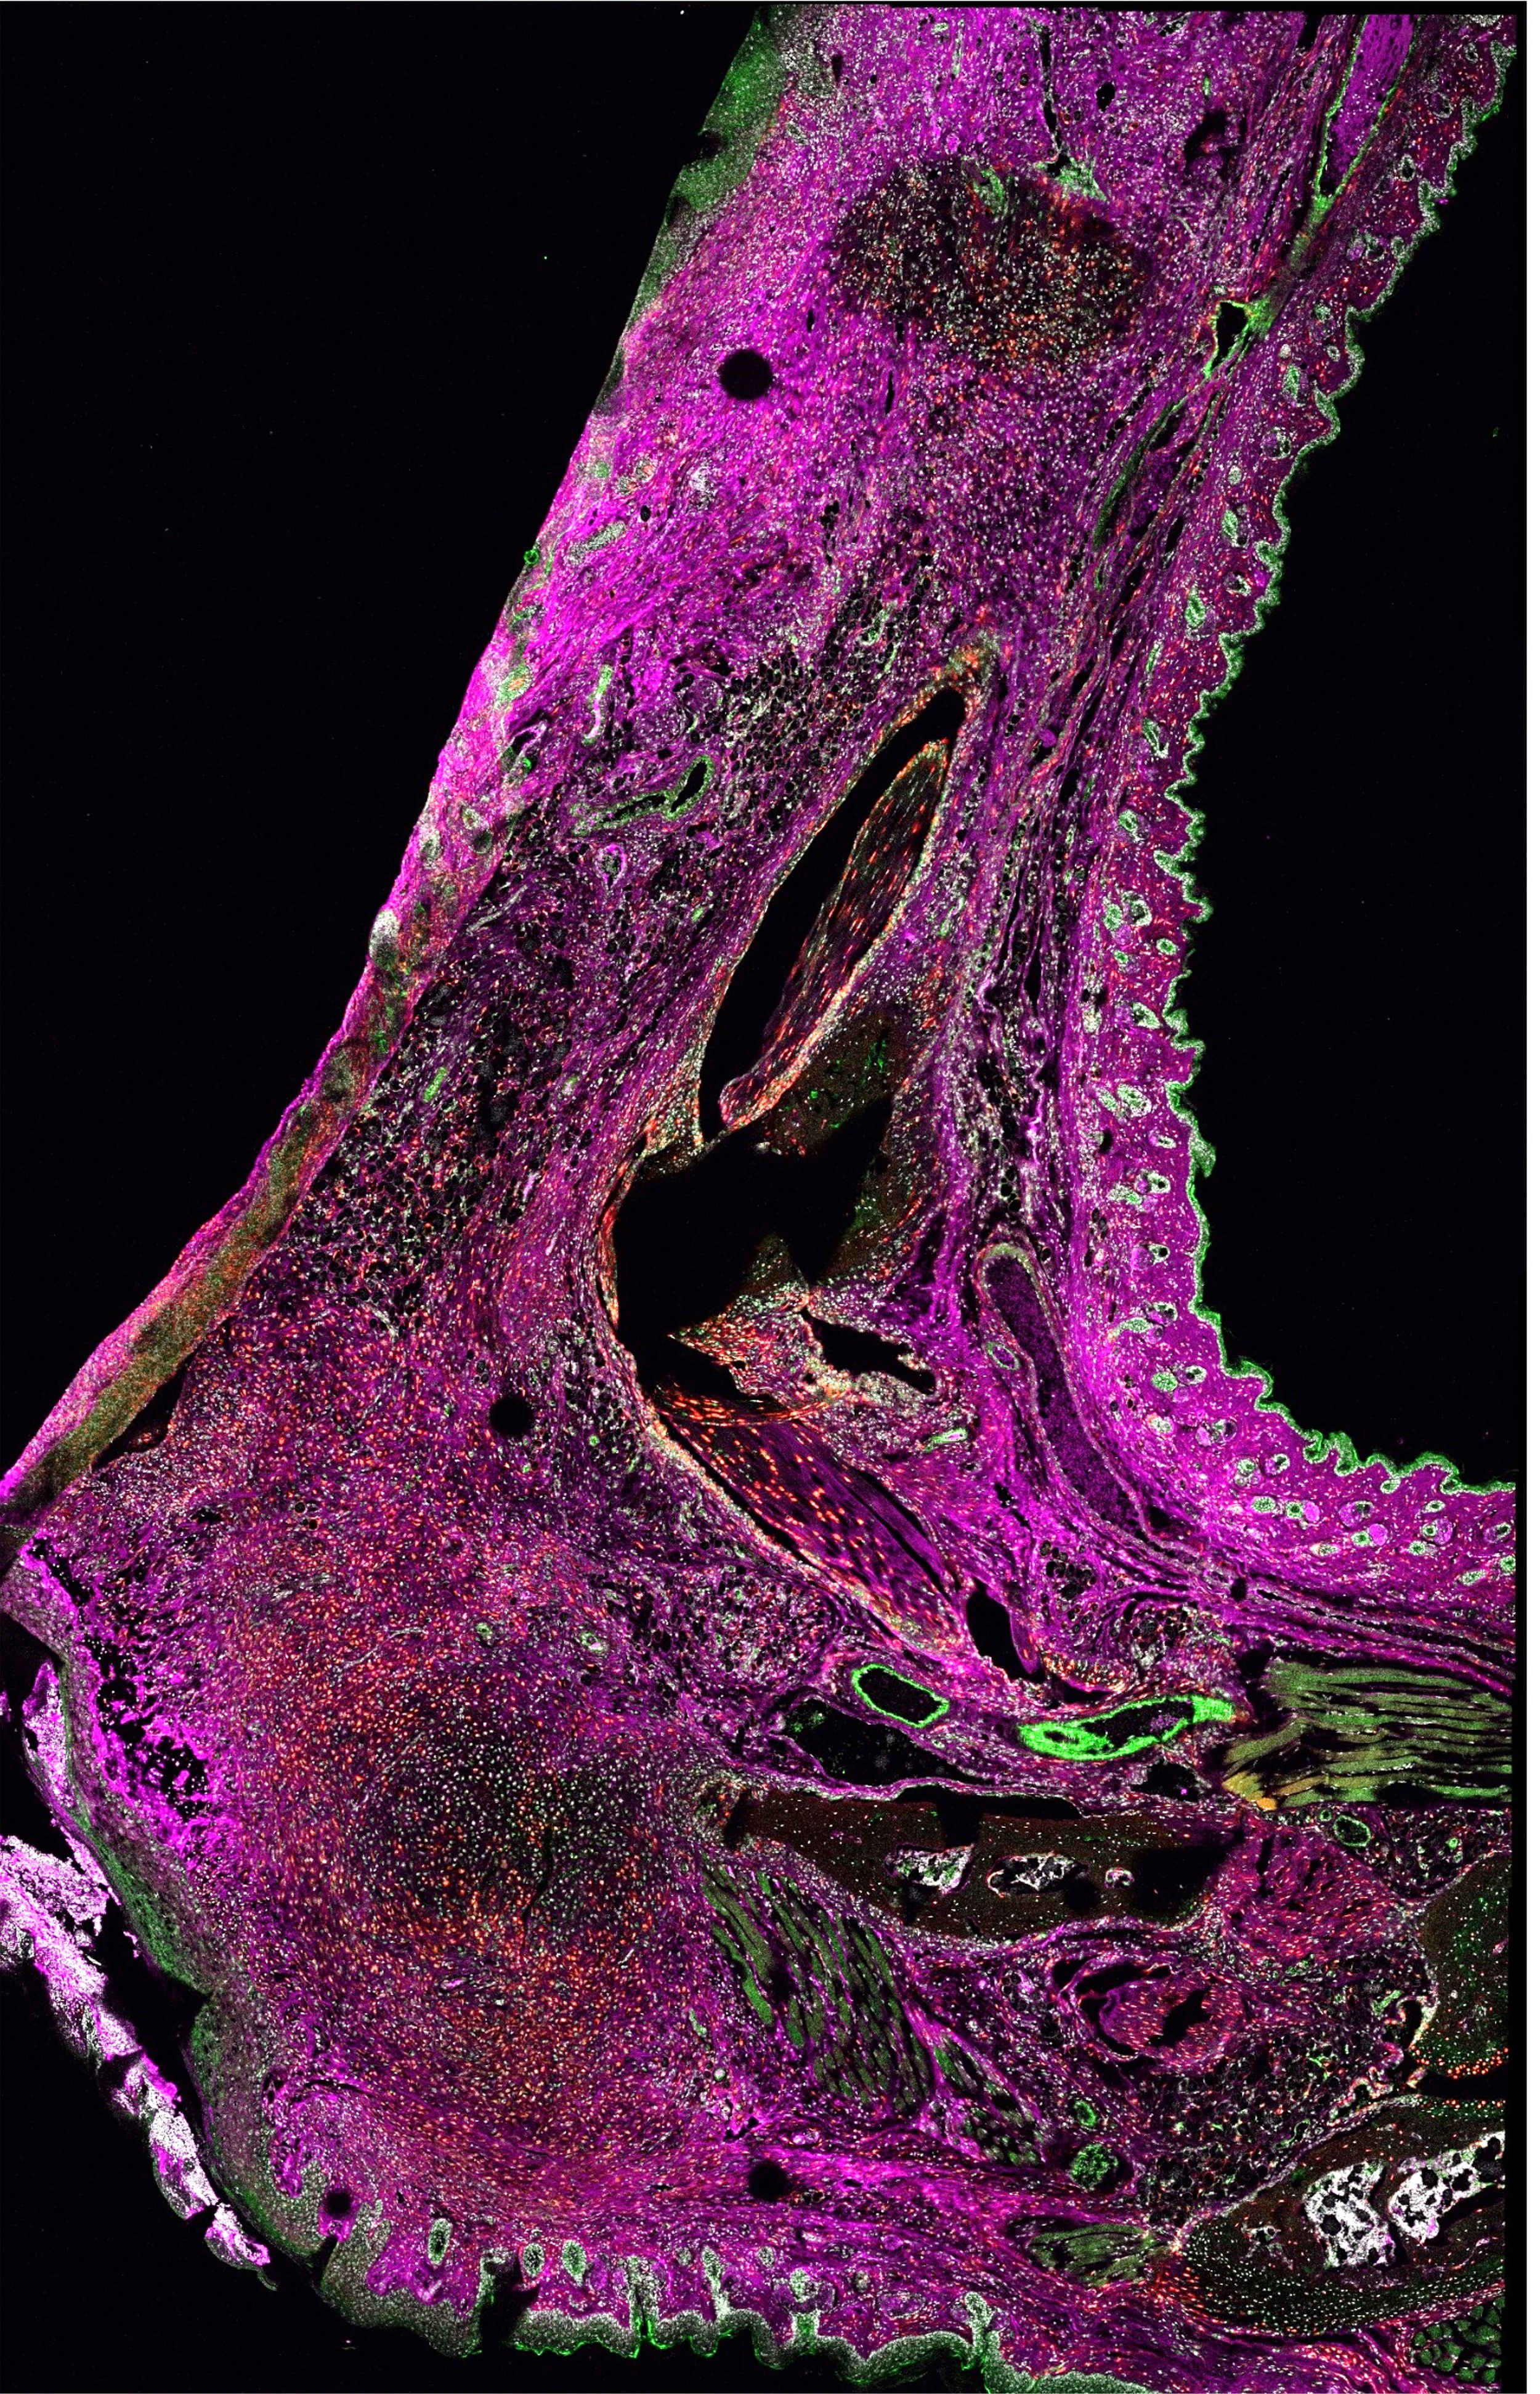

Combinations of advanced techniques such as multiphoton fluorescence and second harmonic generation imaging are used to study tissue remodeling and regeneration. Understanding these processes is critical to developing new therapies for treating blindness due to corneal scarring

Scanning confocal microscopy imaging allows for whole-section, high-resolution imaging to elucidate the spatial expression patterns of proteins of interest (purple).

The Mahendroo Lab uses the mouse as a model system to study term and preterm birth. The focus is to define the molecular steps that transition the cervix from a closed rigid structure to one that opens for a term birth.